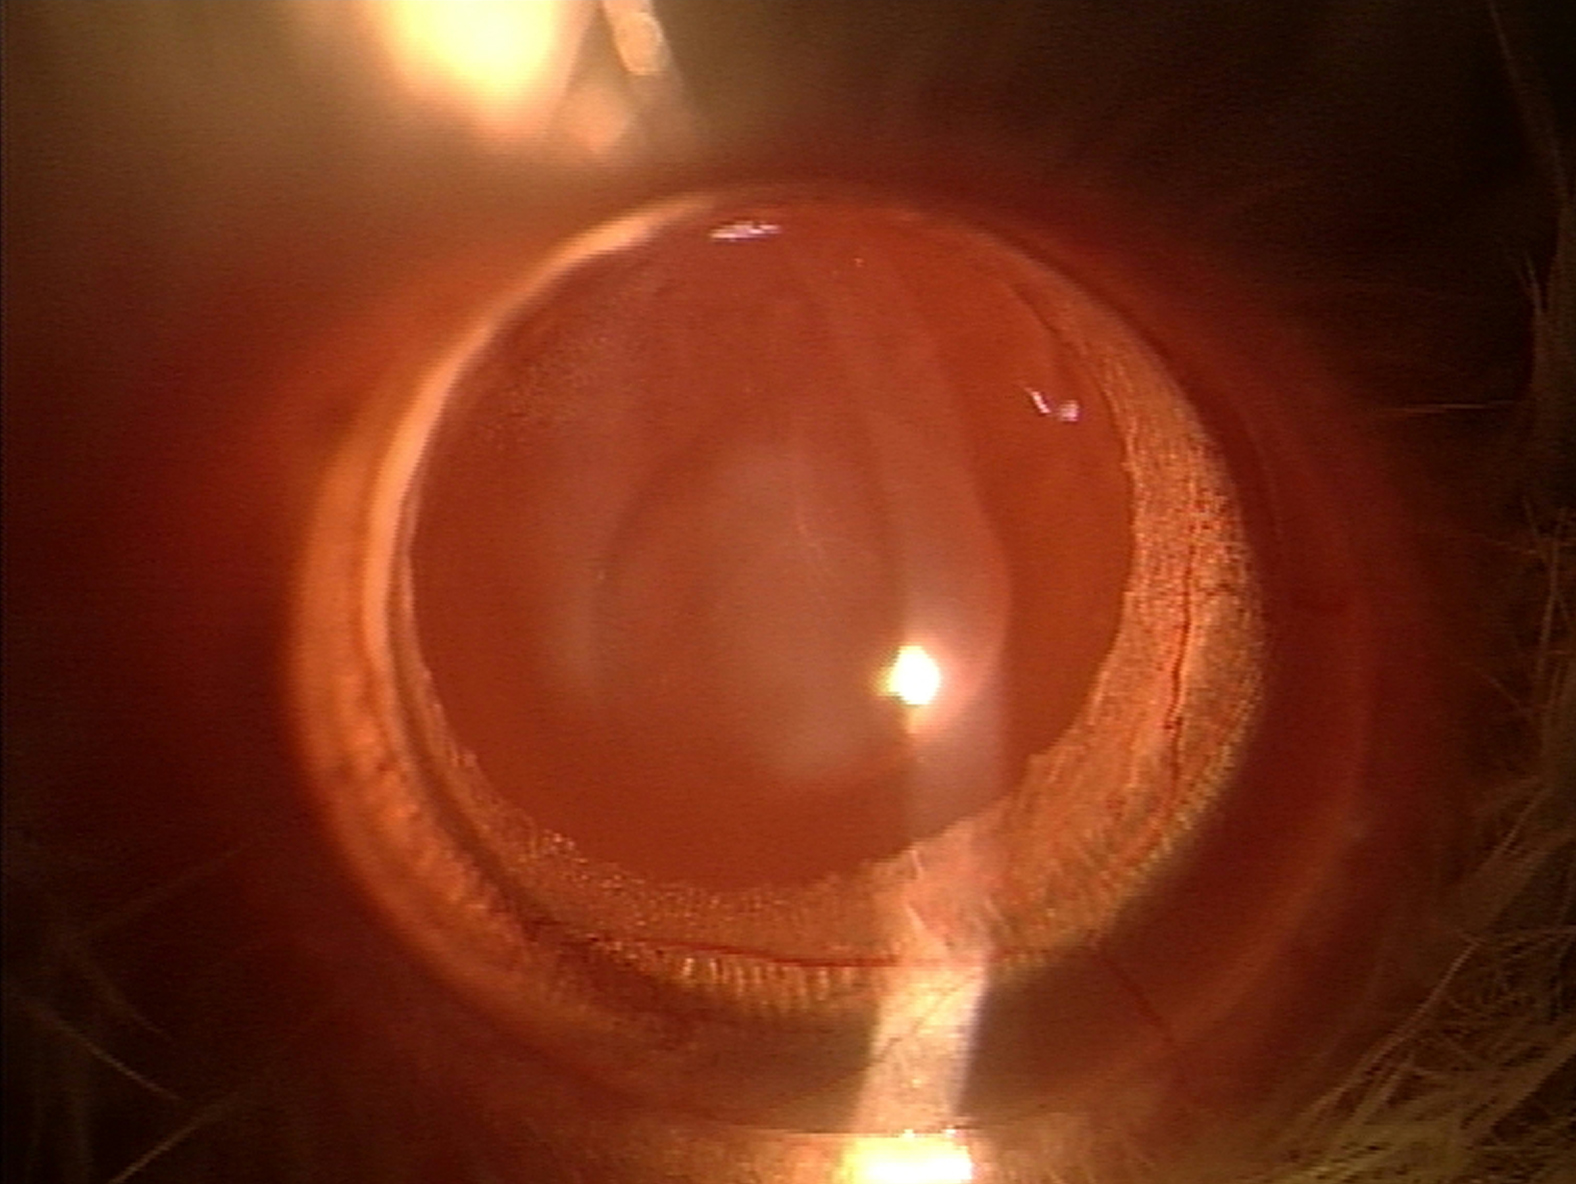

Figure 3 of Elanchezhian, Mol Vis 2009; 15:1485-1491.

Figure 3. Slit-lamp appearance of the eye of 30-day-old Wistar rat pup in group I. This eye exhibited no opacification of the lens (Grade 0 opacification).